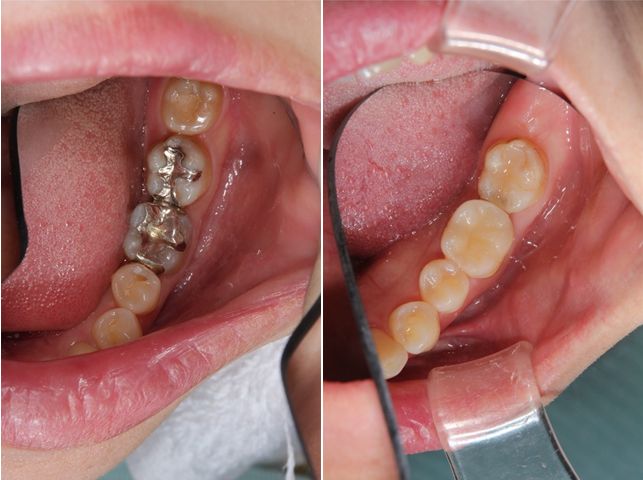

術前術後です。奥歯2本をオールセラミックインレーで治療しました。手前の銀歯はダイレクトボンディングを行いました。

セラミックインレー

費用11万円

リスクとして歯を削る量が多いため痛みが出る可能性と強い力によって割れる可能性がある。

ダイレクトボンディング

費用5万円

リスクとして欠ける可能性がある(修復可能)。